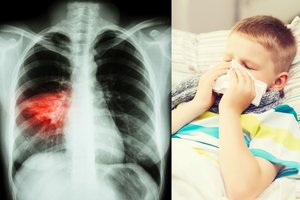

Per metus pasaulyje užregistruojama daugiau kaip 10 mln. šios lėtinės plaučių ligos atvejų. Tuberkuliozė yra infekcinė liga, nuo kurios mūsų laikais miršta daugiausia žmonių – daugiau kaip 1,6 mln. per metus, nors šiai ligai galima užkirsti kelią, be to, laiku pastebėjus ji dažniausiai išgydoma.

Tuberkuliozė egzistavo tūkstantmečius, jos sukėlėjai nepastebimai gyvuoja maždaug ketvirtadalyje žmonijos.

Nors kasmet nužudo beveik tiek pat žmonių, kiek ŽIV/AIDS ir maliarija drauge sudėjus, jau visą šimtmetį nėra naujos, komerciškai prieinamos tuberkuliozės vakcinos.